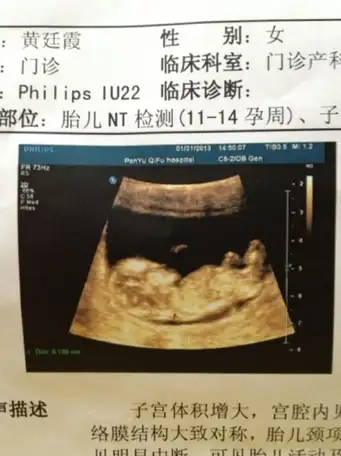

唇腭裂脚趾并联足内翻超声影像四维彩超系统筛查胎儿发育情况

孕3月:胎儿已经有"人样儿"了